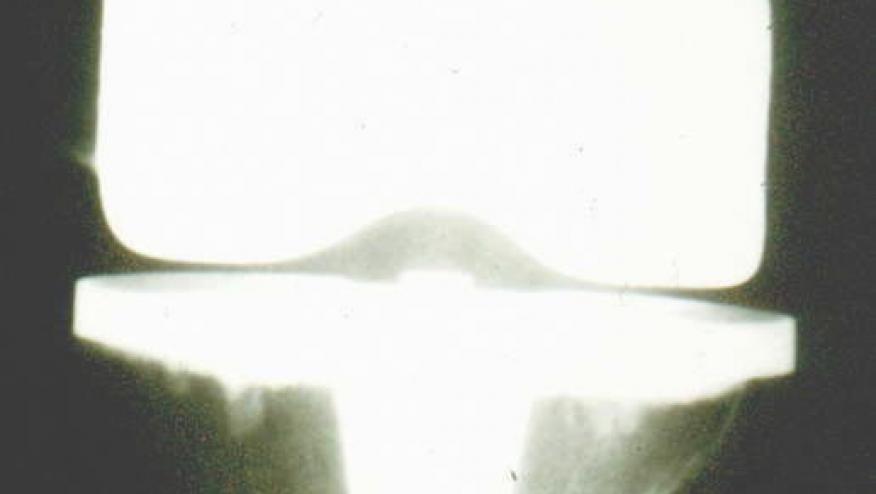

Knee Replacements Last 25 Years Save

UK registry reports that greater than 80% of total knee replacements can last for 25 years.